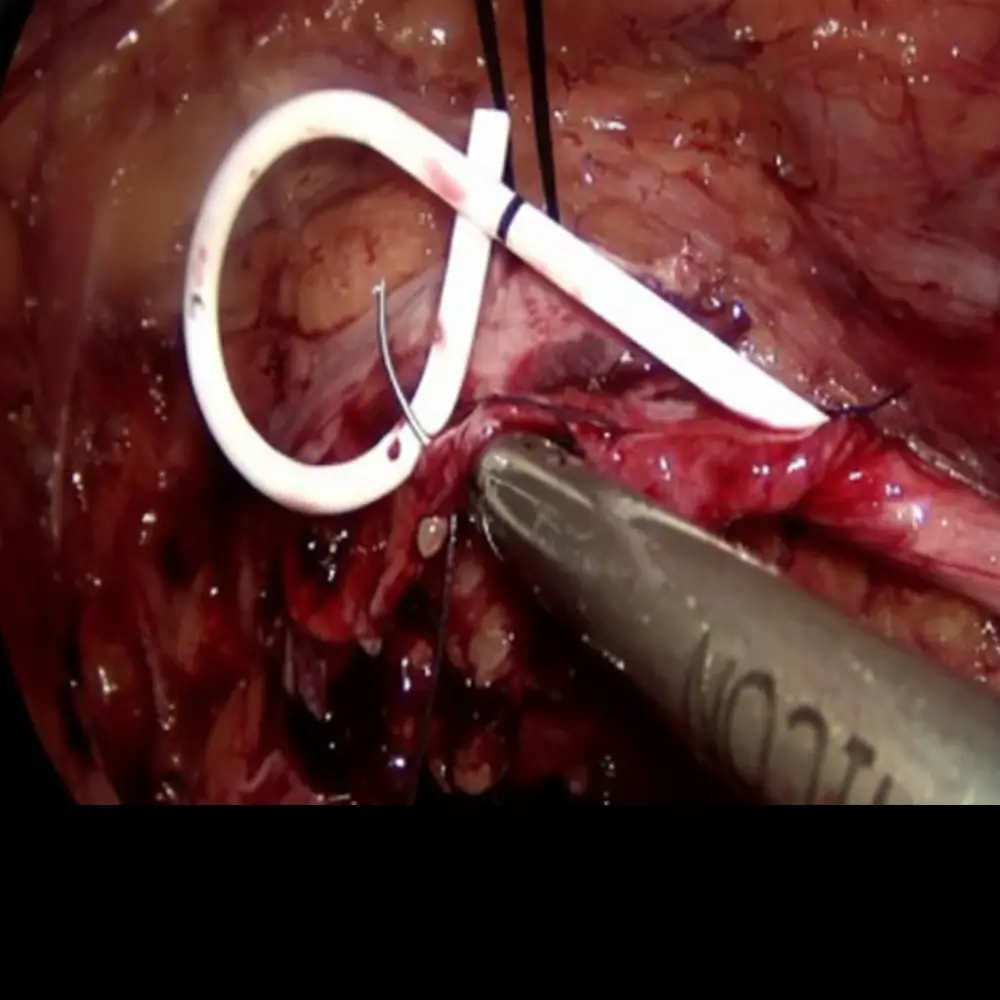

Clinic Procedures Gallery

A visual showcase of advanced urological procedures, highlighting our expertise, technology, and commitment to patient care.